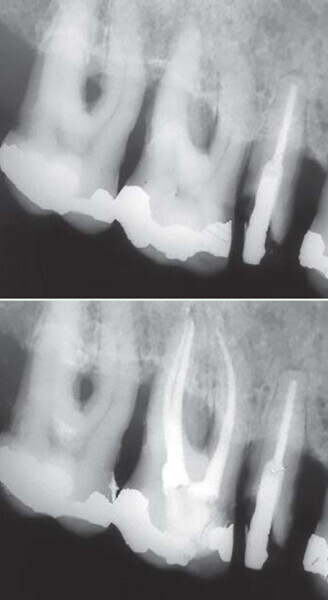

Figs. 1 : Cas clinique réalisé avec le système Genius (c Dr Carlos Spironell Ramos).

Fig. 11 : Cas clinique Dr Carlos Spironelli.